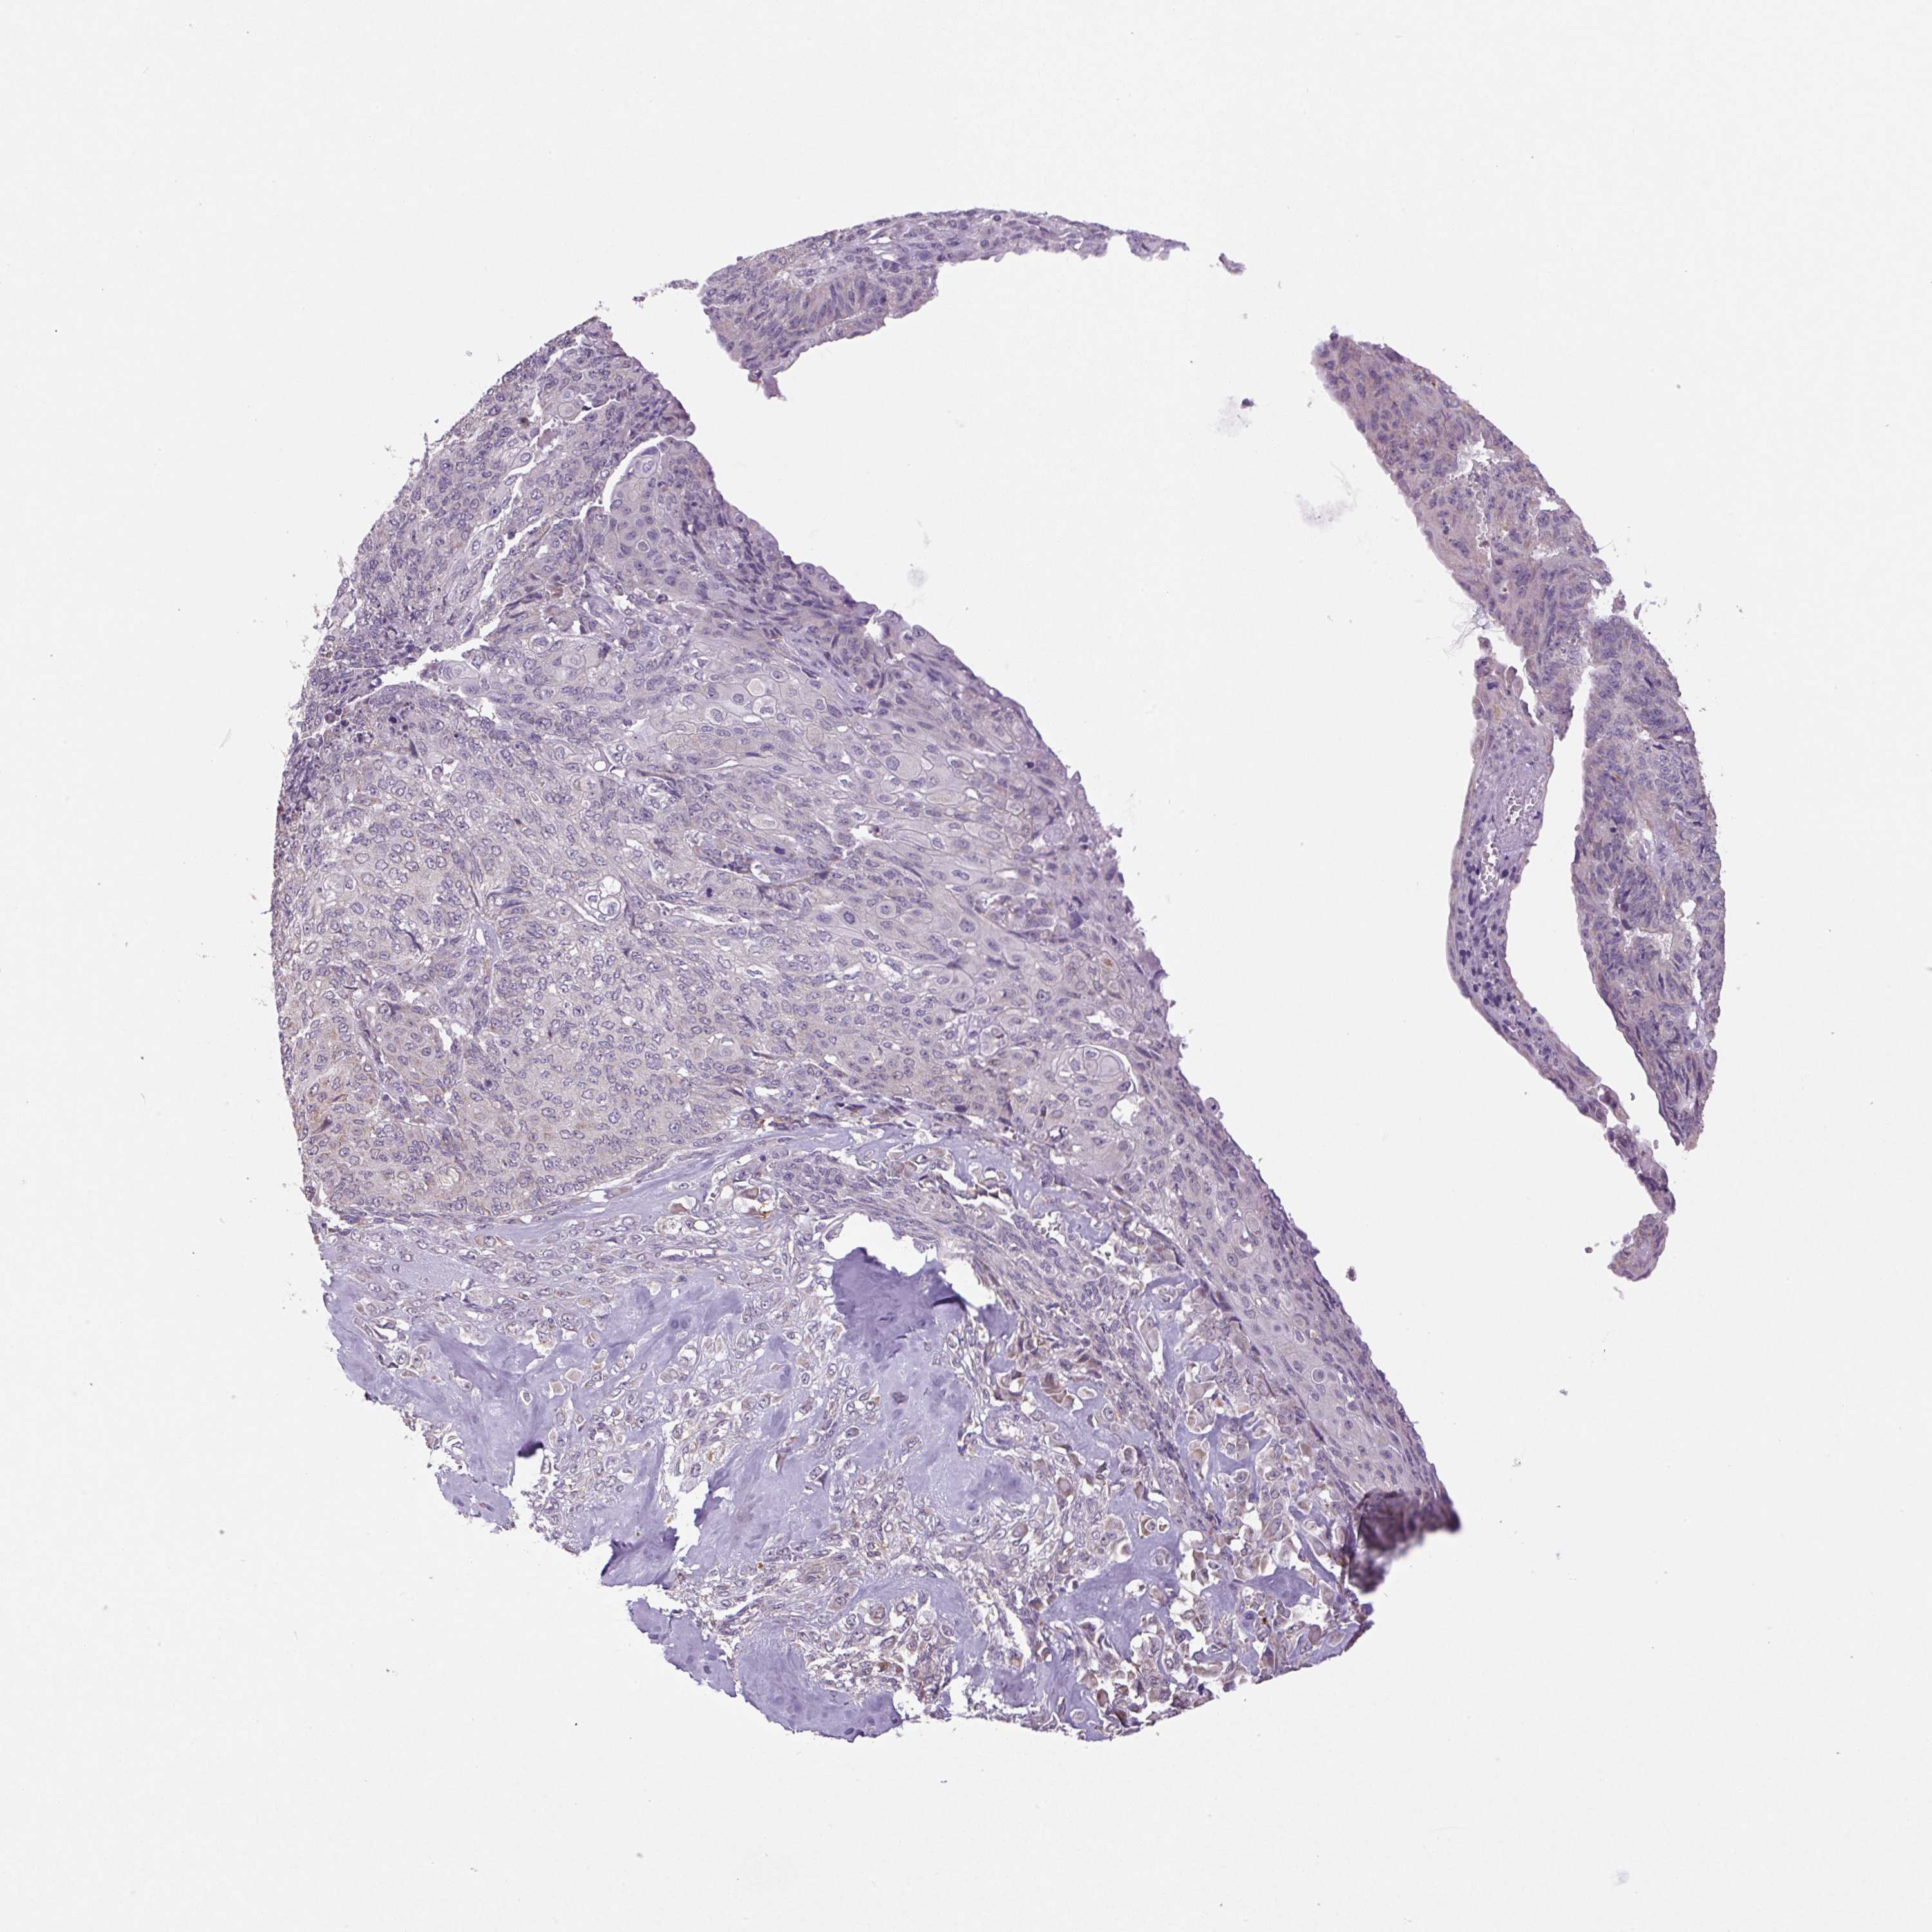

ENDOMETRIAL CANCER - Protein expressioni

A mouse-over function shows sample information and annotation data. Click on an image to view it in a full screen mode. Samples can be filtered based on level of antibody staining by selecting one or several of the following categories: high, medium, low and not detected. The assay and annotation is described here.

Note that samples used for immunohistochemistry by the Human Protein Atlas do not correspond to samples in the TCGA dataset.

Antibody stainingi

Antibody staining in the annotated cell types in the current human tissue is reported as not detected, low, medium, or high, based on conventional immunohistochemistry profiling in selected tissues. This score is based on the combination of the staining intensity and fraction of stained cells.

Each image is clickable and will lead to virtual microscopy that enables deeper exploration of all samples and also displays staining intensity scores, fraction scores and subcellular localization as well as patient and tissue information for each sample.

Antibody HPA052590

Antibody HPA053608

Staining

High

Medium

Low

Not detected

Intensity

Strong

Moderate

Weak

Negative

Quantity

>75%

75%-25%

<25%

None

Location

Nuclear

Cytoplasmic/membranous

Cytoplasmic/membranous,nuclear

Adenocarcinoma, NOS

Adenocarcinoma, metastatic, NOS